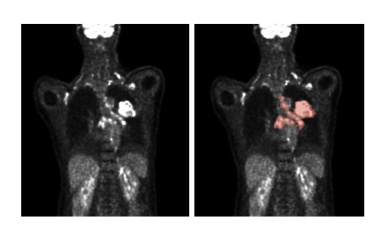

Künstliche Intelligenz: Algorithmen verbessern Analyse medizinischer Bilder

Künstliche Intelligenz kann die Auswertung von medizinischen Bilddaten verbessern. So können auf Deep Learning basierende Algorithmen die Lage und Größe von Tumoren feststellen.